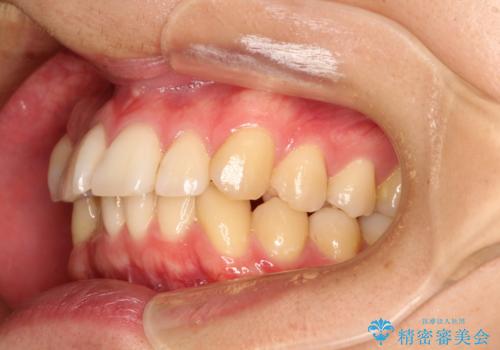

前歯の凸凹をきれいにしたい。インビザラインによる治療

- 前歯の凸凹を主訴に来院された患者様です。

インビザラインにて治療を行いました。